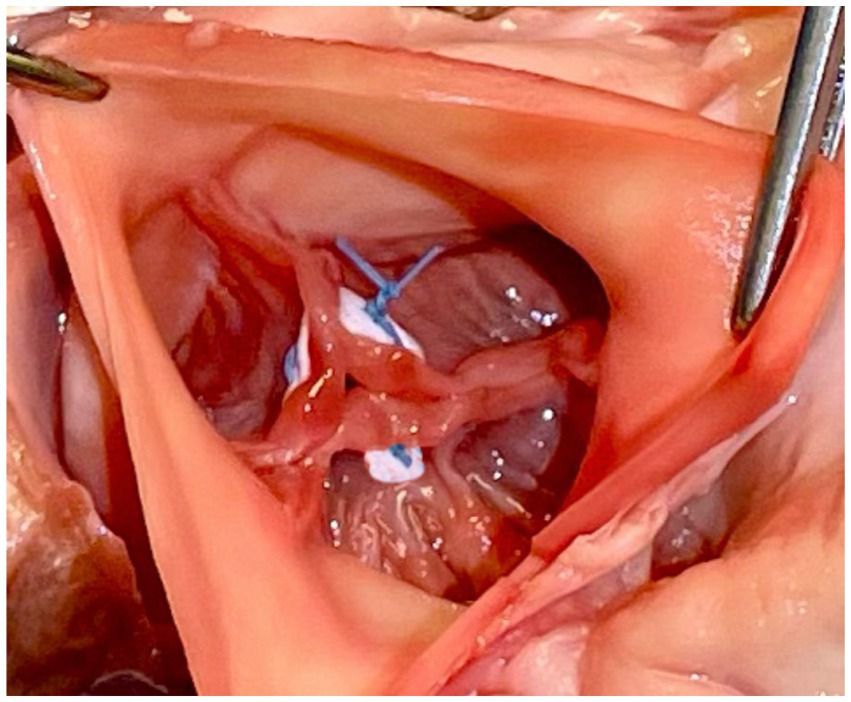

Park’s stitch

In this technique, pledgeted 4-0 Prolene sutures approximate the fibrous nodules of Arantius creating a coaptation stitch. This approach allows the AV to still open for ejection, even though the effective orifice area of AV is markedly diminished (1) (Figures 4, 5).

Figure 4

Park’s stitch. Pledgeted 4-0 Prolene sutures are applied to approximate the fibrous nodules of Arantius to create a coaptation stitch. Reproduced with permission from (1).

Figure 5

Modified park’s stitch.